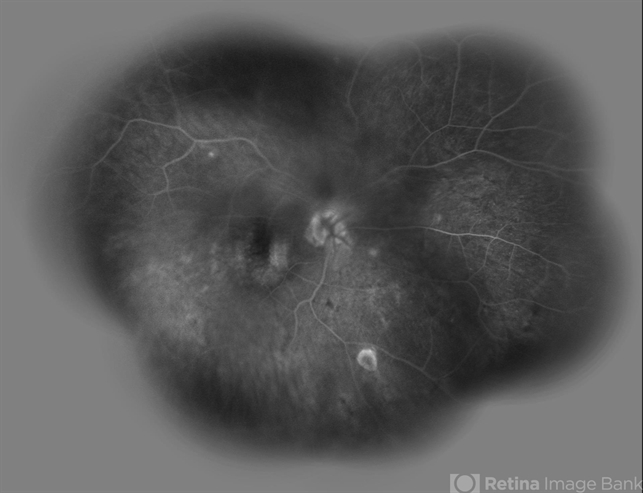

- radiation maculopathy, radiation retinopathy

- Solmaz Shahmohammad, Negah Eye Center, Tehran

- Heidelberg Spectralis

- Late phase wide- field FA image of the right eye of a 65-year-old man with radiation maculopathy and retinopathy.